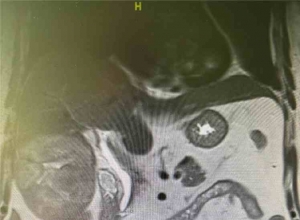

| 选择性腹腔镜结肠切除右盲肠扭转--病例报告及文献复习 Colectomía derecha laparoscópica electiva por vólvulo cecal: reporte de un caso y revisión de la literatura Elective laparoscopic right colectomy for caecal volvulus: case report and literature review Abstract 摘要 Background 背景 Caecal volvulus is an uncommon cause of intestinal obstruction. Its clinical presentation is non-specific, with the diagnosis usually confirmed by barium enema and abdominal computed tomography. Treatment depends on many factors, and minimally invasive approaches are becoming the treatment of choice. 盲肠扭转是一种罕见的肠梗阻的原因。它的临床表现是非特异性的,诊断通常通过钡剂灌肠和腹部计算机断层扫描。治疗取决于许多因素,微创治疗成为首选的治疗方法。 Clinic case 临床案例 A 54 years old female, admitted to the Emergency Department with clinical symptoms of intestinal obstruction. On physical examination she had a palpable, firm, and tympanitic mass in the right abdomen, with peritoneal irritation. The radiographs of the abdomen, barium enema and abdominal computed tomography showed caecal volvulus. As she showed a full remission after the barium enema, with no clinical or biochemical data of systemic inflammatory response syndrome or peritoneal irritation, she was discharged to her home. Two weeks later, a laparoscopic right hemicolectomy was performed with an ileo-transverse extracorporeal anastomosis. Her progress was satisfactory, and she was discharged 4 days after surgery due to improvement. 一位54岁的女性,住进急诊科,有临床症状的肠梗阻。体检时她有一个显而易见的,坚定的,在右腹部臌胀的肿块,伴腹膜刺激。腹部的X线平片、钡灌肠及腹部电脑断层扫描显示盲肠扭转。由于她在钡灌肠后表现完全缓解,没有全身性炎症反应综合征或腹膜刺激的临床或生化数据,她出院回家了。两周后,腹腔镜右半结肠切除术和回肠吻合术进行横向体外吻合。她的进展是令人满意的,她在手术后4天,由于改善出院。 Conclusion 结论 Caecal volvulus is a rare cause of intestinal obstruction, with high mortality rates, and is caused by excessive mobility of the caecum. Its incidence is increasing. Treatment depends on many factors. Early non-surgical untwisting, followed by an elective laparoscopic surgical procedure offers several advantages and reduces mortality. 盲肠扭转是肠梗阻的罕见病因,死亡率高,是由盲肠过度的流动性造成的。其发病率增加。治疗取决于许多因素。早期非手术解除梗阻,其次是为择期腹腔镜手术提供了几个优势,降低死亡率。 Keywords 关键词 Caecal volvulus; Computed tomography of the abdomen; Laparoscopic colectomy; Elective surgery 盲肠扭转;腹部计算机断层摄影术;腹腔镜结肠切除术;选择性外科手术 Figura 1. Placa simple de abdomen de pie con dilatación cecal (flecha negra), niveles hidroaéreos (flechas blancas) y ausencia de aire en ámpula rectal (flecha negra punteada). 图1.简单腹部站立与盲肠扩张(黑色箭头),空气流体水平(白色箭头)和直肠壶腹没有空气的条件(黑色虚线箭头)。 Figura 2. Colon por enema donde se observa imagen en grano de café (flechas blancas). 图2.结肠灌肠,观察到的咖啡豆样图像(白色箭头)。 Figura 3. Tomografía de abdomen. Corte axial con dilatación cecal, nivel hidroaéreo, sin evidencia de neumatosis intestinal ni líquido libre. 图3.腹部CT扫描。轴向切割盲肠扩张,液位没有肠道积气或游离液体的证据。 Figura 4. Laparoscopia final donde se observa íleo transverso anastomosis latero lateral. 图4.腹腔镜横结肠梗阻端侧吻合观察到的很少。 Figura 5. Esquema que ilustra el vólvulo cecal con torsión axial del ciego, colon ascendente e íleon terminal. 图5. 盲肠扭转模式说明了盲肠轴向扭转,升结肠及回肠末端。 Figura 6. Esquema que ilustra la báscula cecal donde se produce un punto de flexión del ciego hacia arriba y anterior del colon ascendente, que provoca un mecanismo valvular de oclusión. 图6. 方案说明发生在盲肠的一点向上弯曲前盲升结肠的机制,导致瓣膜闭塞。 原文: |